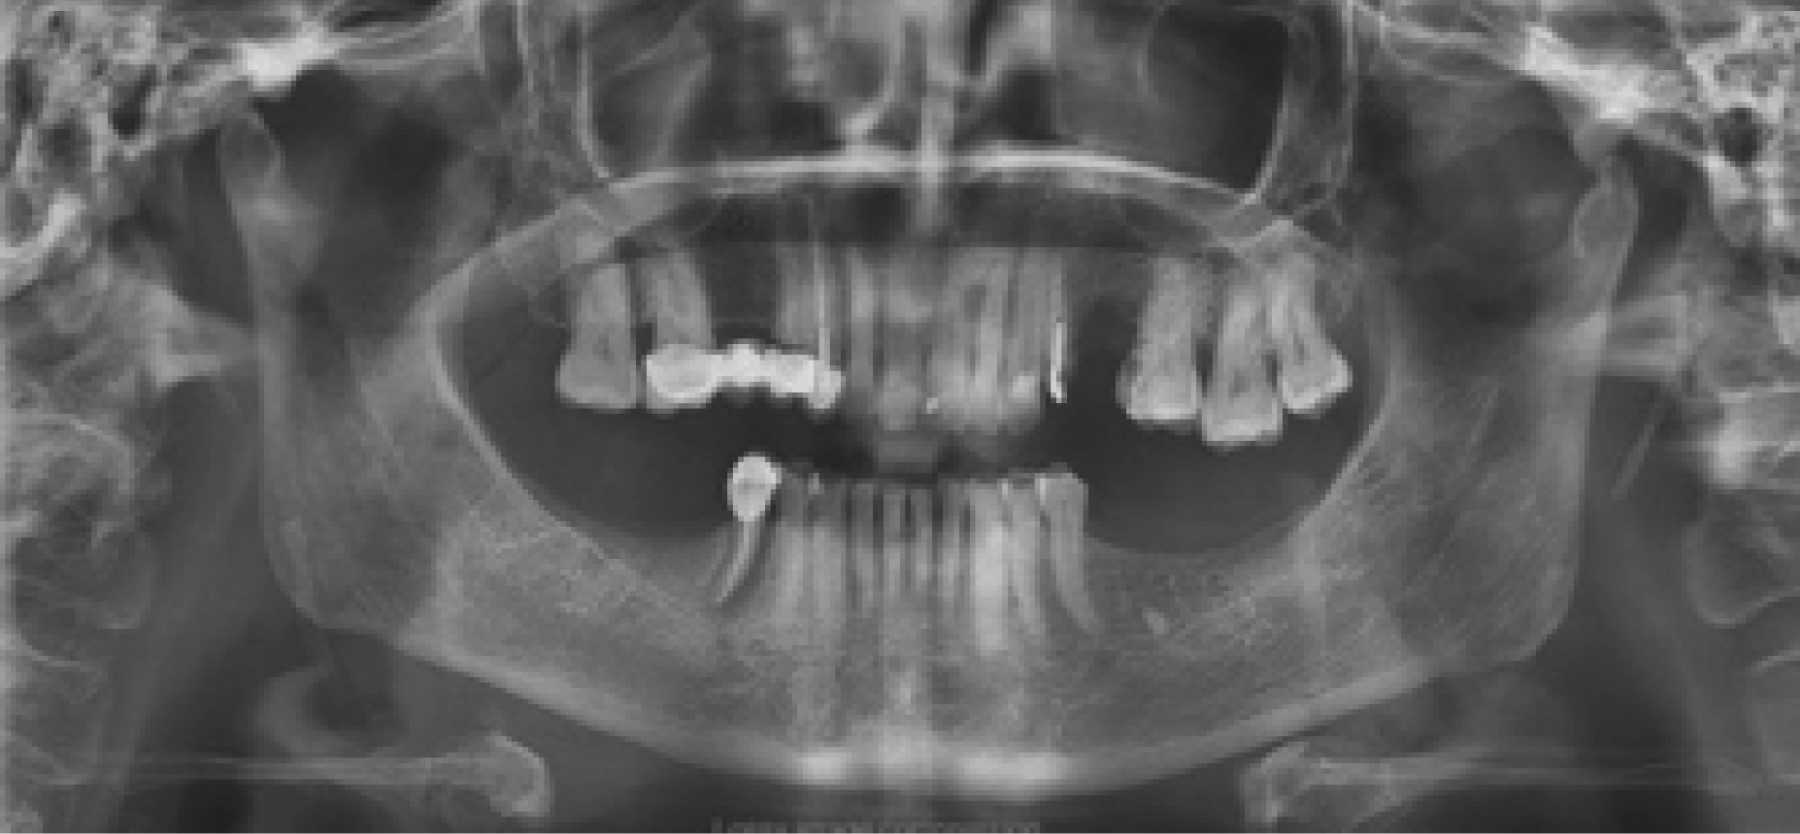

De los 500 pacientes incluidos en este estudio, 336 (67%) pacientes correspondieron al género femenino y 164 (33%) al masculino, con una media de edad de 43 años (mínimo de cinco años y máximo de 91 años con una desviación estándar de 20.7). En 239 (47%) pacientes no se observaron alteraciones. Los principales hallazgos fueron los siguientes: 226 (45%) casos con pérdida ósea de proceso alveolar, seguido de hallazgos radiográficos sugestivos de alteración en la zona articular (ATM) con 171 (34%) casos; en 151 (30%) casos se observaron signos radiográficos de calcificación del ligamento estilohioideo (CLE-síndrome de Eagle) (Figura 1); 18 (3%) casos presentaron estructuras correspondientes a calcificación de carótida (CC) y en 11 (2%) casos se localizaron zonas radiolúcidas semejantes a lesiones quísticas (Figura 2). Los hallazgos se reportan en la Tabla 1.

Respecto a la muestra de CLE (Figura 3), el expediente clínico de 51 pacientes indica que presentaron síntomas relacionados con síndrome de Eagle (SE), mismos que se describen en la Figura 4. Otras de las patologías encontradas fueron las calcificaciones de la carótida en 18 casos (Figura 5), sin que se asociaran con alguna manifestación clínica, o hubieran sido detectadas en el expediente clínico.7,8